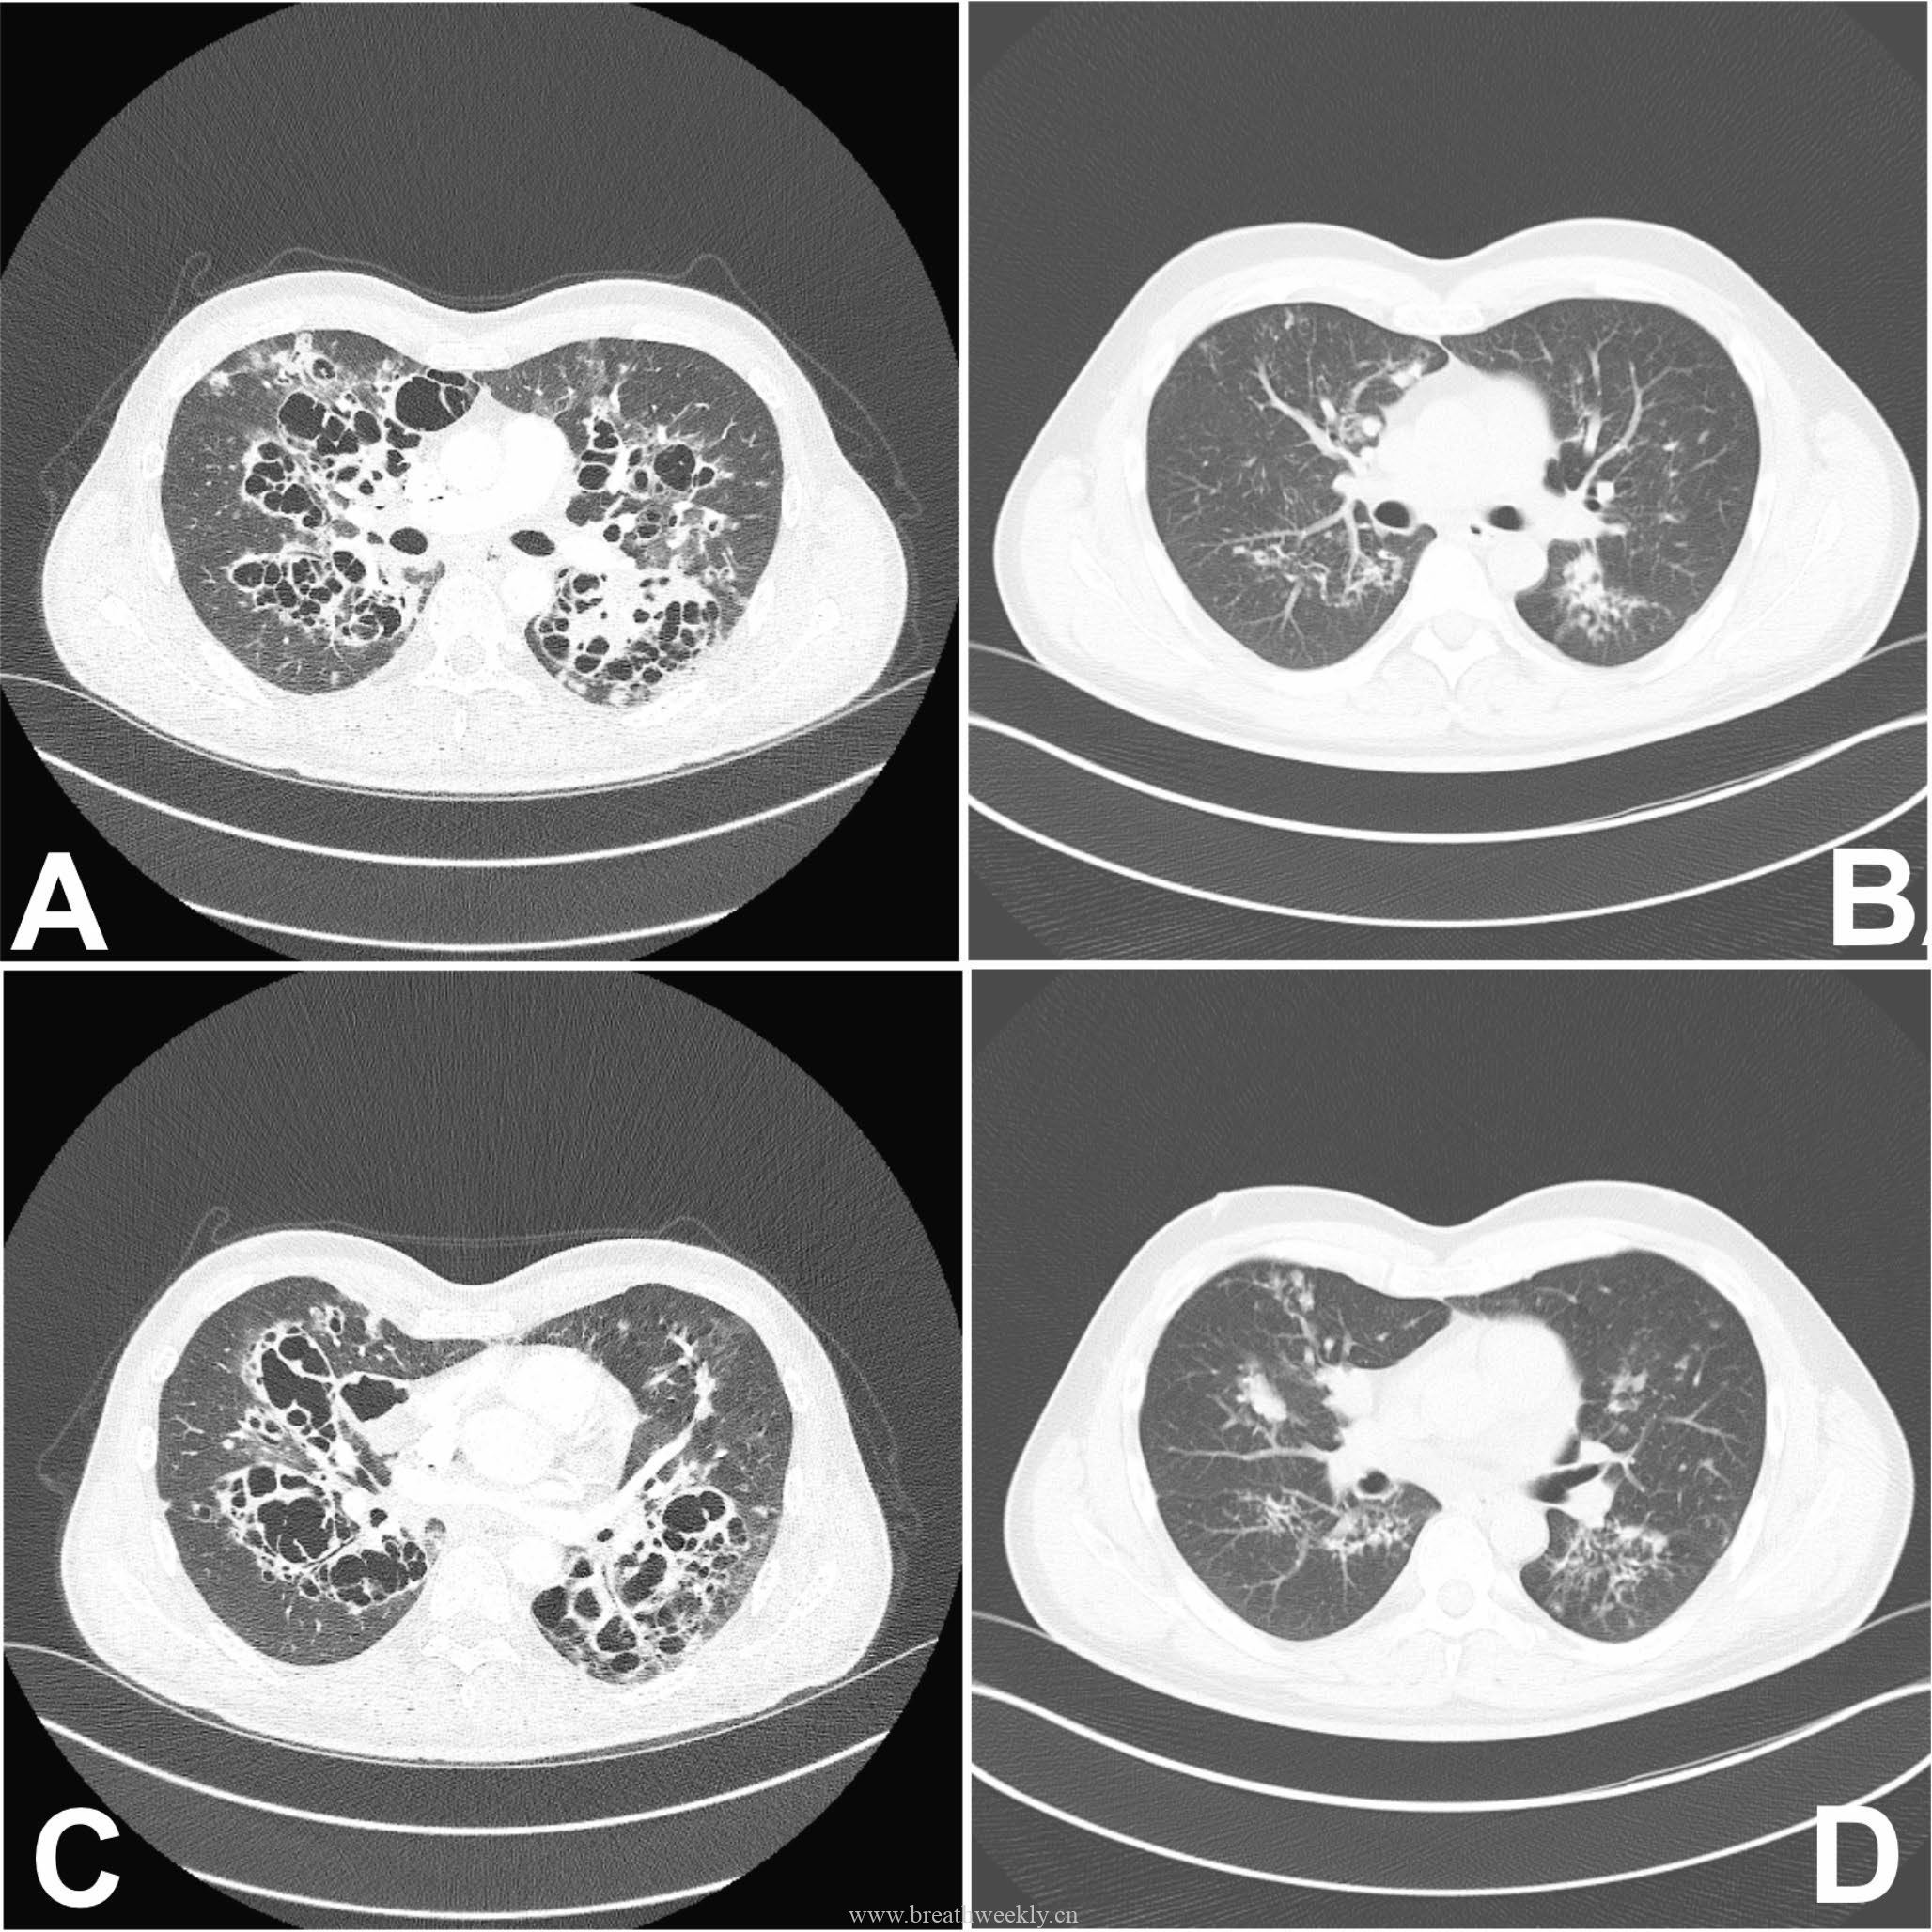

影像学检查

头颅CT除外颅内肿块及脑出血。脑及颈椎MRI(增强)除外CT隐性病灶,但发现右侧胸廓入口处囊性病灶。颈部超声及增强胸部CT:右侧上纵隔囊性占位,位于甲状腺右叶后下方,内见结节性实性成分及上极供血血管。胸部CT示前纵隔预期胸腺位置无异常软组织,提示胸腺脂肪萎缩。

⁹ᵐTc – 甲氧基异丁基异腈甲状旁腺显像:早期及延迟图像均可见甲状腺右叶下方异常摄取灶,摄取位于右上纵隔囊性病灶的实性成分内。

临床过程:因纵隔病灶位置位于甲状腺右叶后下方,术前考虑异位胸腺瘤或异位甲状旁腺腺瘤。CT及超声示无claw sign,排除甲状腺来源。99mTc-Sestamibi显像定位病灶。MG予糖皮质激素及IV免疫球蛋白治疗效果良好;高钙血症予IV补液及cinacalcet治疗。最终行机器人辅助纵隔甲状旁腺腺瘤及胸腺切除术,病理确诊甲状旁腺腺瘤。术后患者恢复良好。